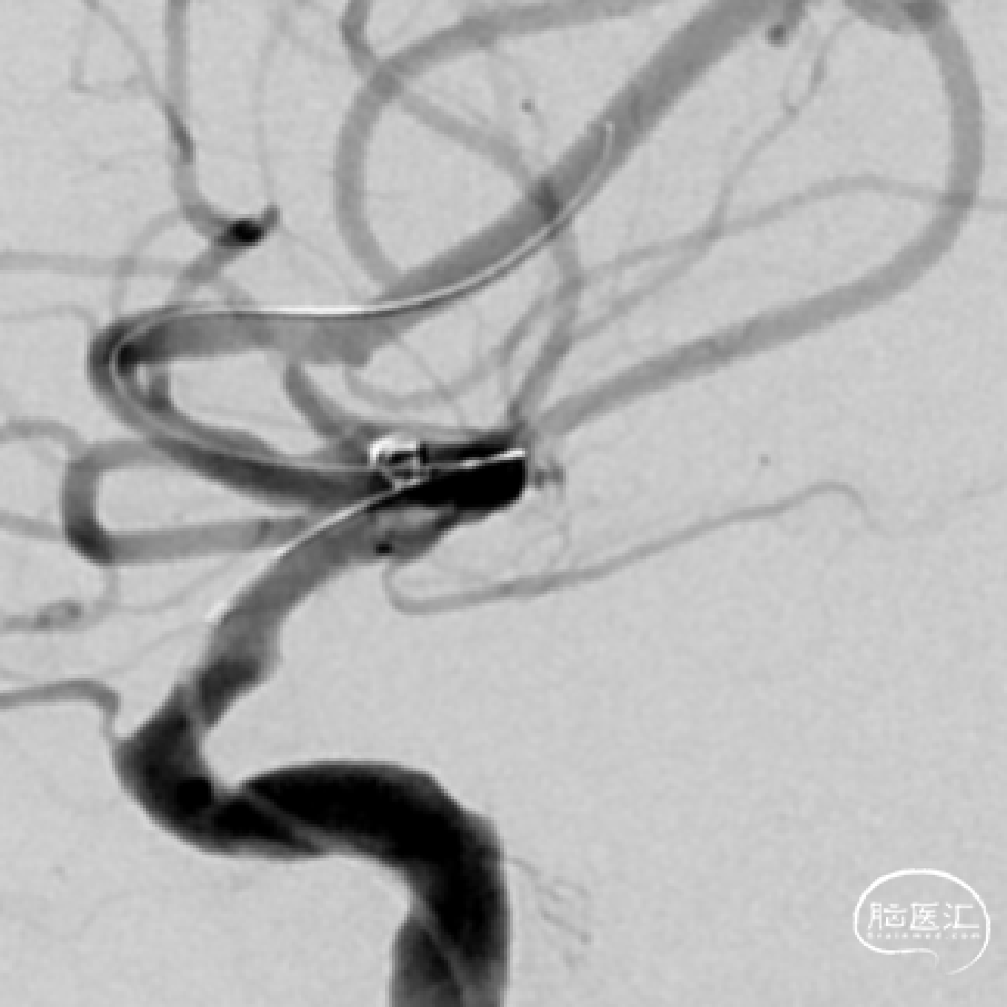

➢DSA(2023.11.10)

R-DAS技术超选右侧颈内,右侧颈内动脉血管迂曲。

颅内球囊 2.25*15mm扩张,扩张至10个atm。

狭窄改善。

植入Atlas支架,动脉瘤不显示,狭窄改善。

术后正侧位。